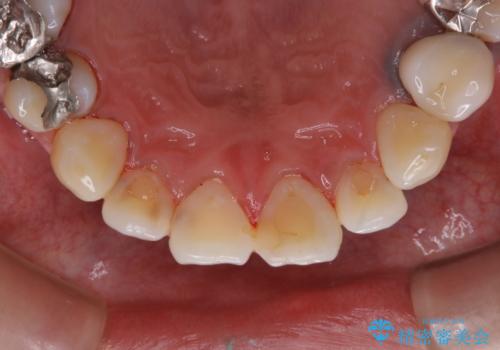

- 虫歯治療を始める前に、まずはしっかり汚れを取りたいとのことで来院されました。歯石やステインが分厚く付着していたため、PMTC60分コースを行いました。

歯の表面に、茶色く色が残っている所がありますが、これは詰め物の変色によるものです。以前に、CR(コンポジットレジン)による虫歯治療がされています。

CRは経年的劣化や、着色してしまうことがあります。PMTCでクリーニングを行うと、古いCRが目立つことがあるため、気になる際は詰め替えを行います。

茶色くなっている部分が、着色なのか、劣化なのか、虫歯によるものなのかは判別が難しいことがあります。そのため、定期的にPMTCを行うことで状態の確認が的確に行えます。